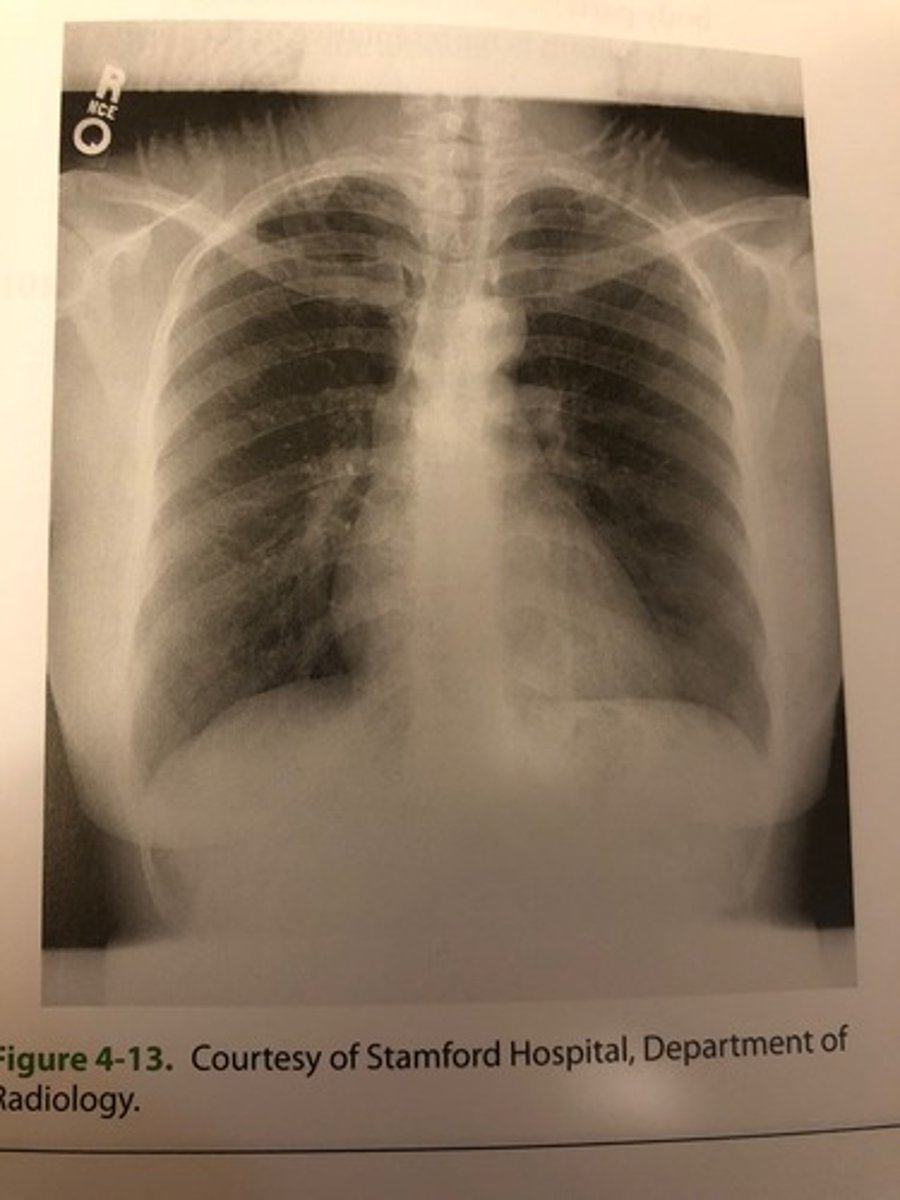

The radiograph shown in Figure 4-13 demonstrates an example of

(A) motion blur

(B) underexposure

(C) scanner/reader artifact

(D) exposure artifact

Exposure-type artifacts include

1. double exposure

2. motion

3. image fading

A. 1 only

B. 1 and 2 only

C. 2 and 3 only

D. 1, 2, and 3

(B) I and 2 only